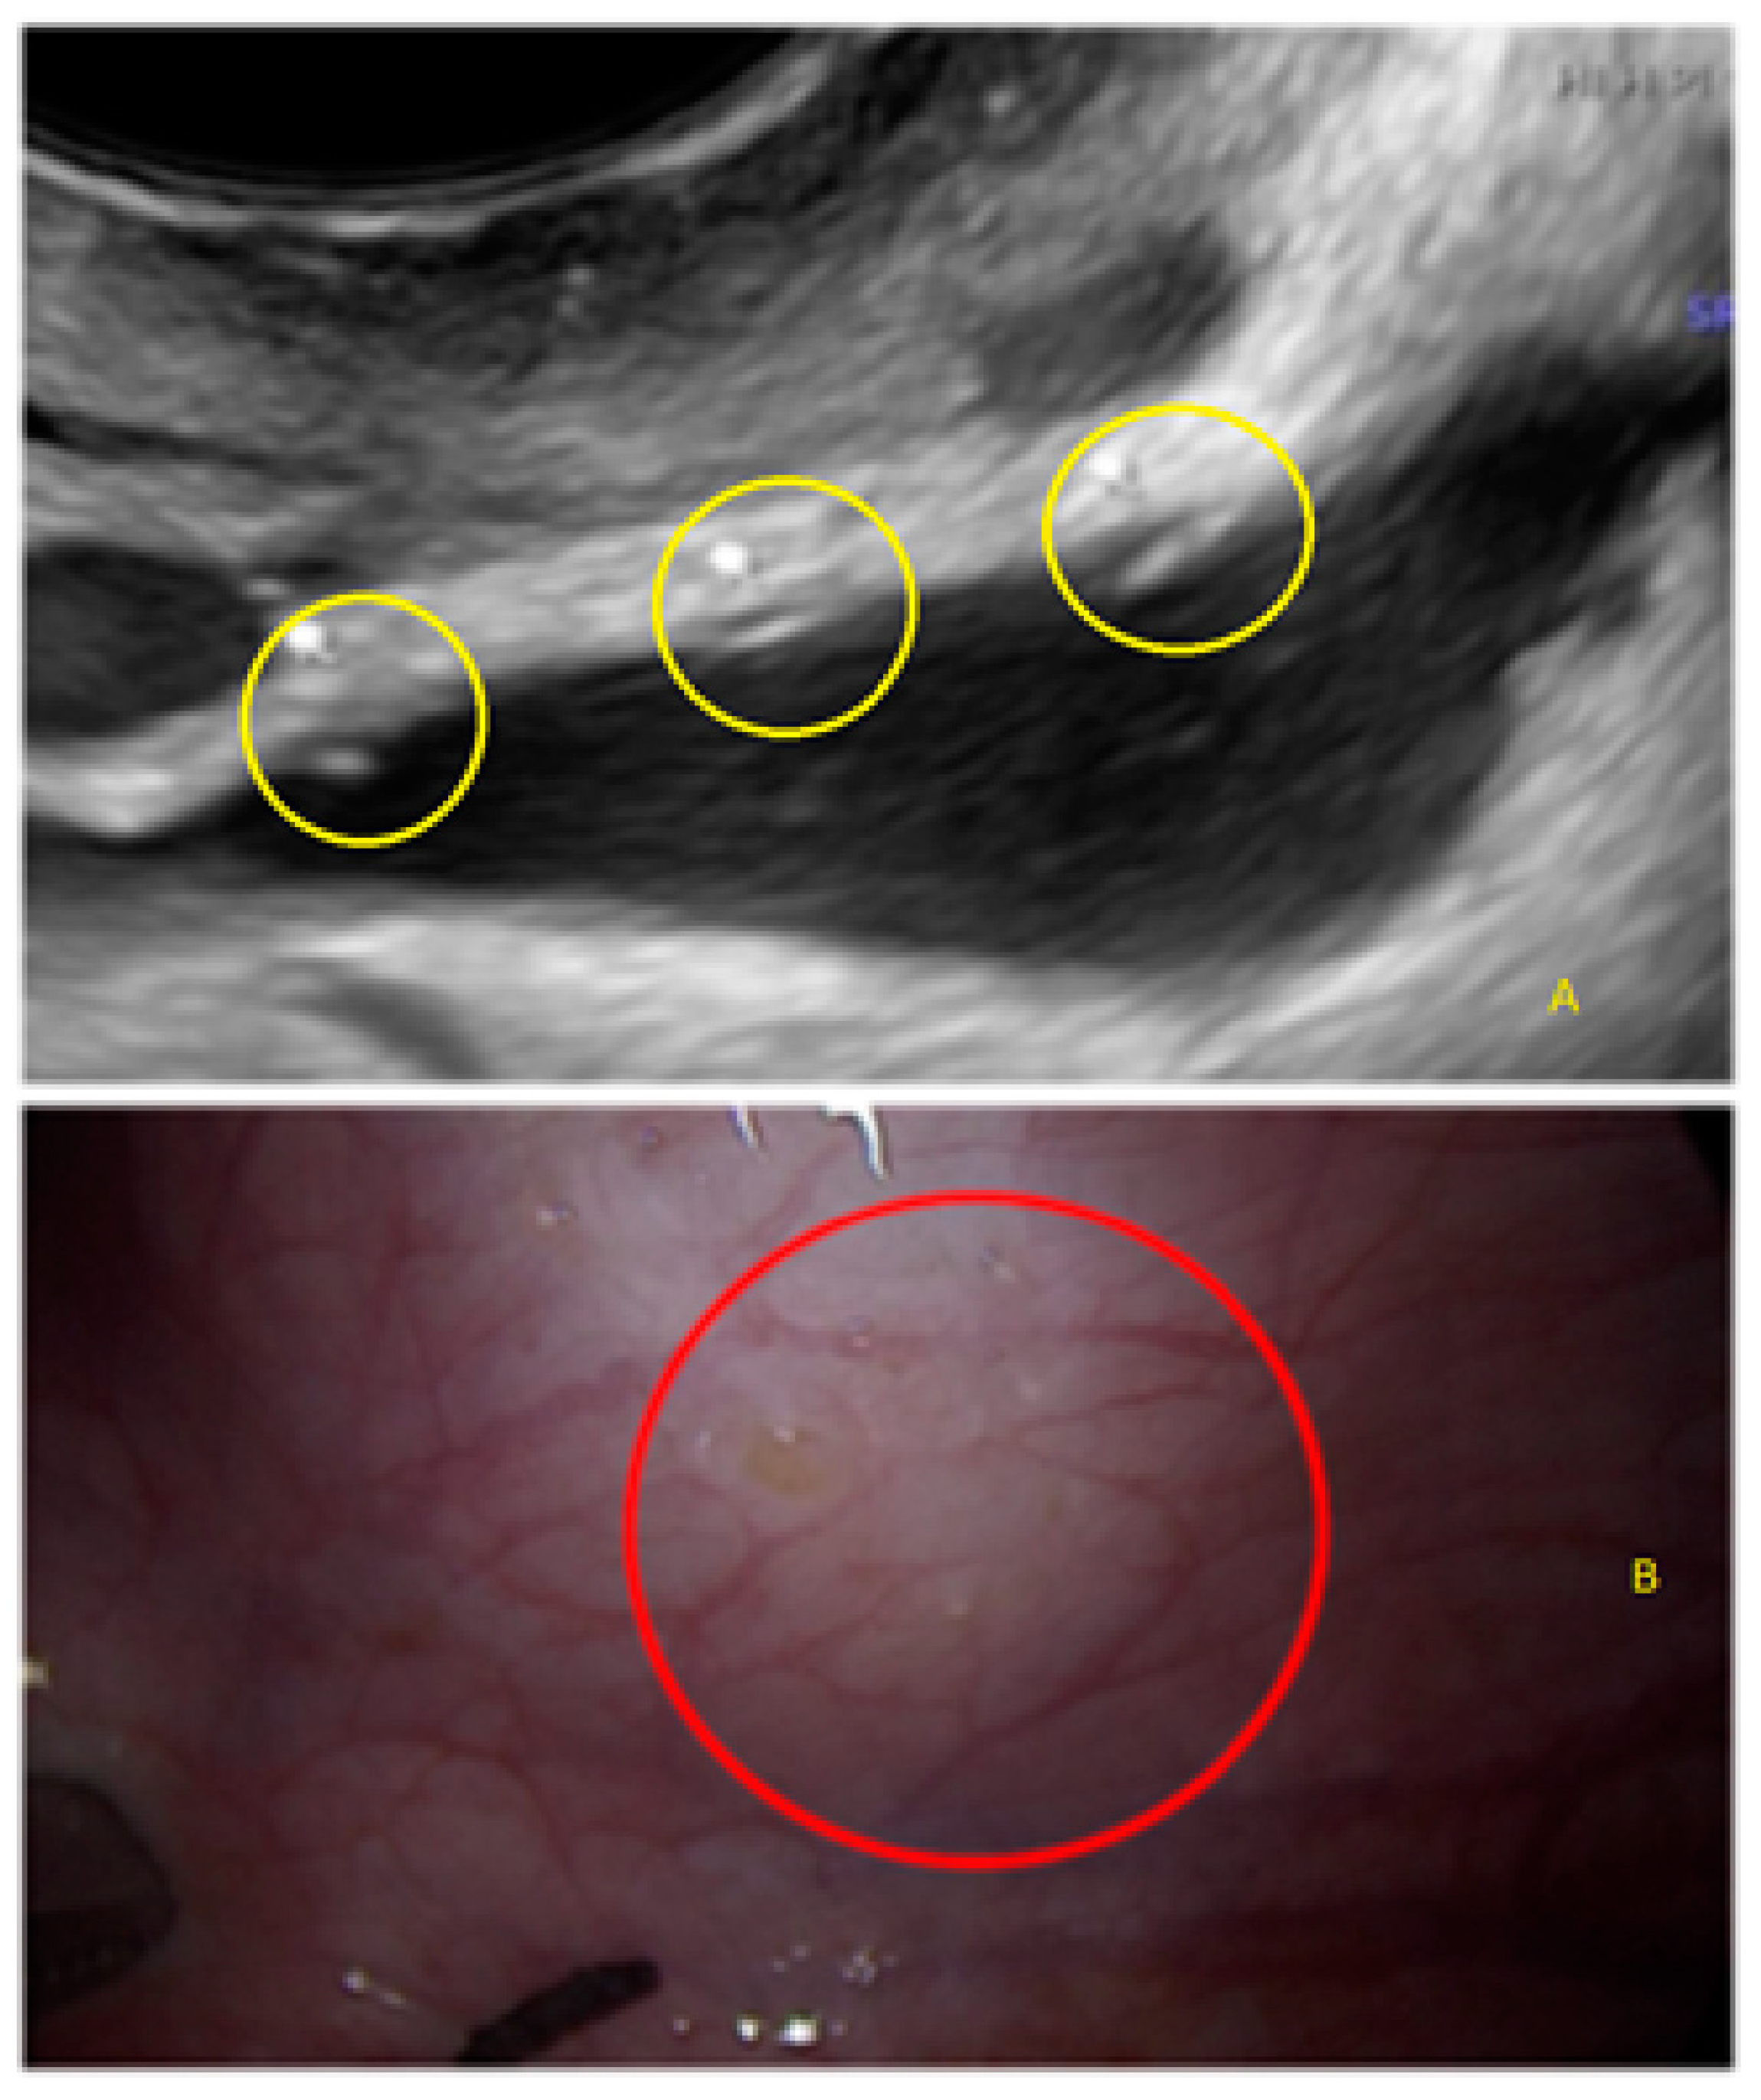

- The presence of hyperechoic foci (we called this a “pearl”).

3.1. Cystic Solitary Lesion

3.2. Cystic Multiple Separate Lesions

3.3. Cystic Lesions Arranged in a Cluster